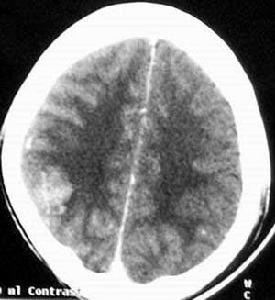

4、頭顱CT可見局部混合密度區,增強後可見不規則增強區,並可見迂曲擴張血管,還可以發現血腫和腦萎縮局部鈣化等繼發性改變。

腦動靜脈畸形④電子計算機X射線斷層成像(CT),在增強的CT檢查時80%病例可見畸形病變。CT不能代替血管造影,但可發現腦的併發症如腦萎縮(盜血所致)、血腫、梗塞和腦積水等。